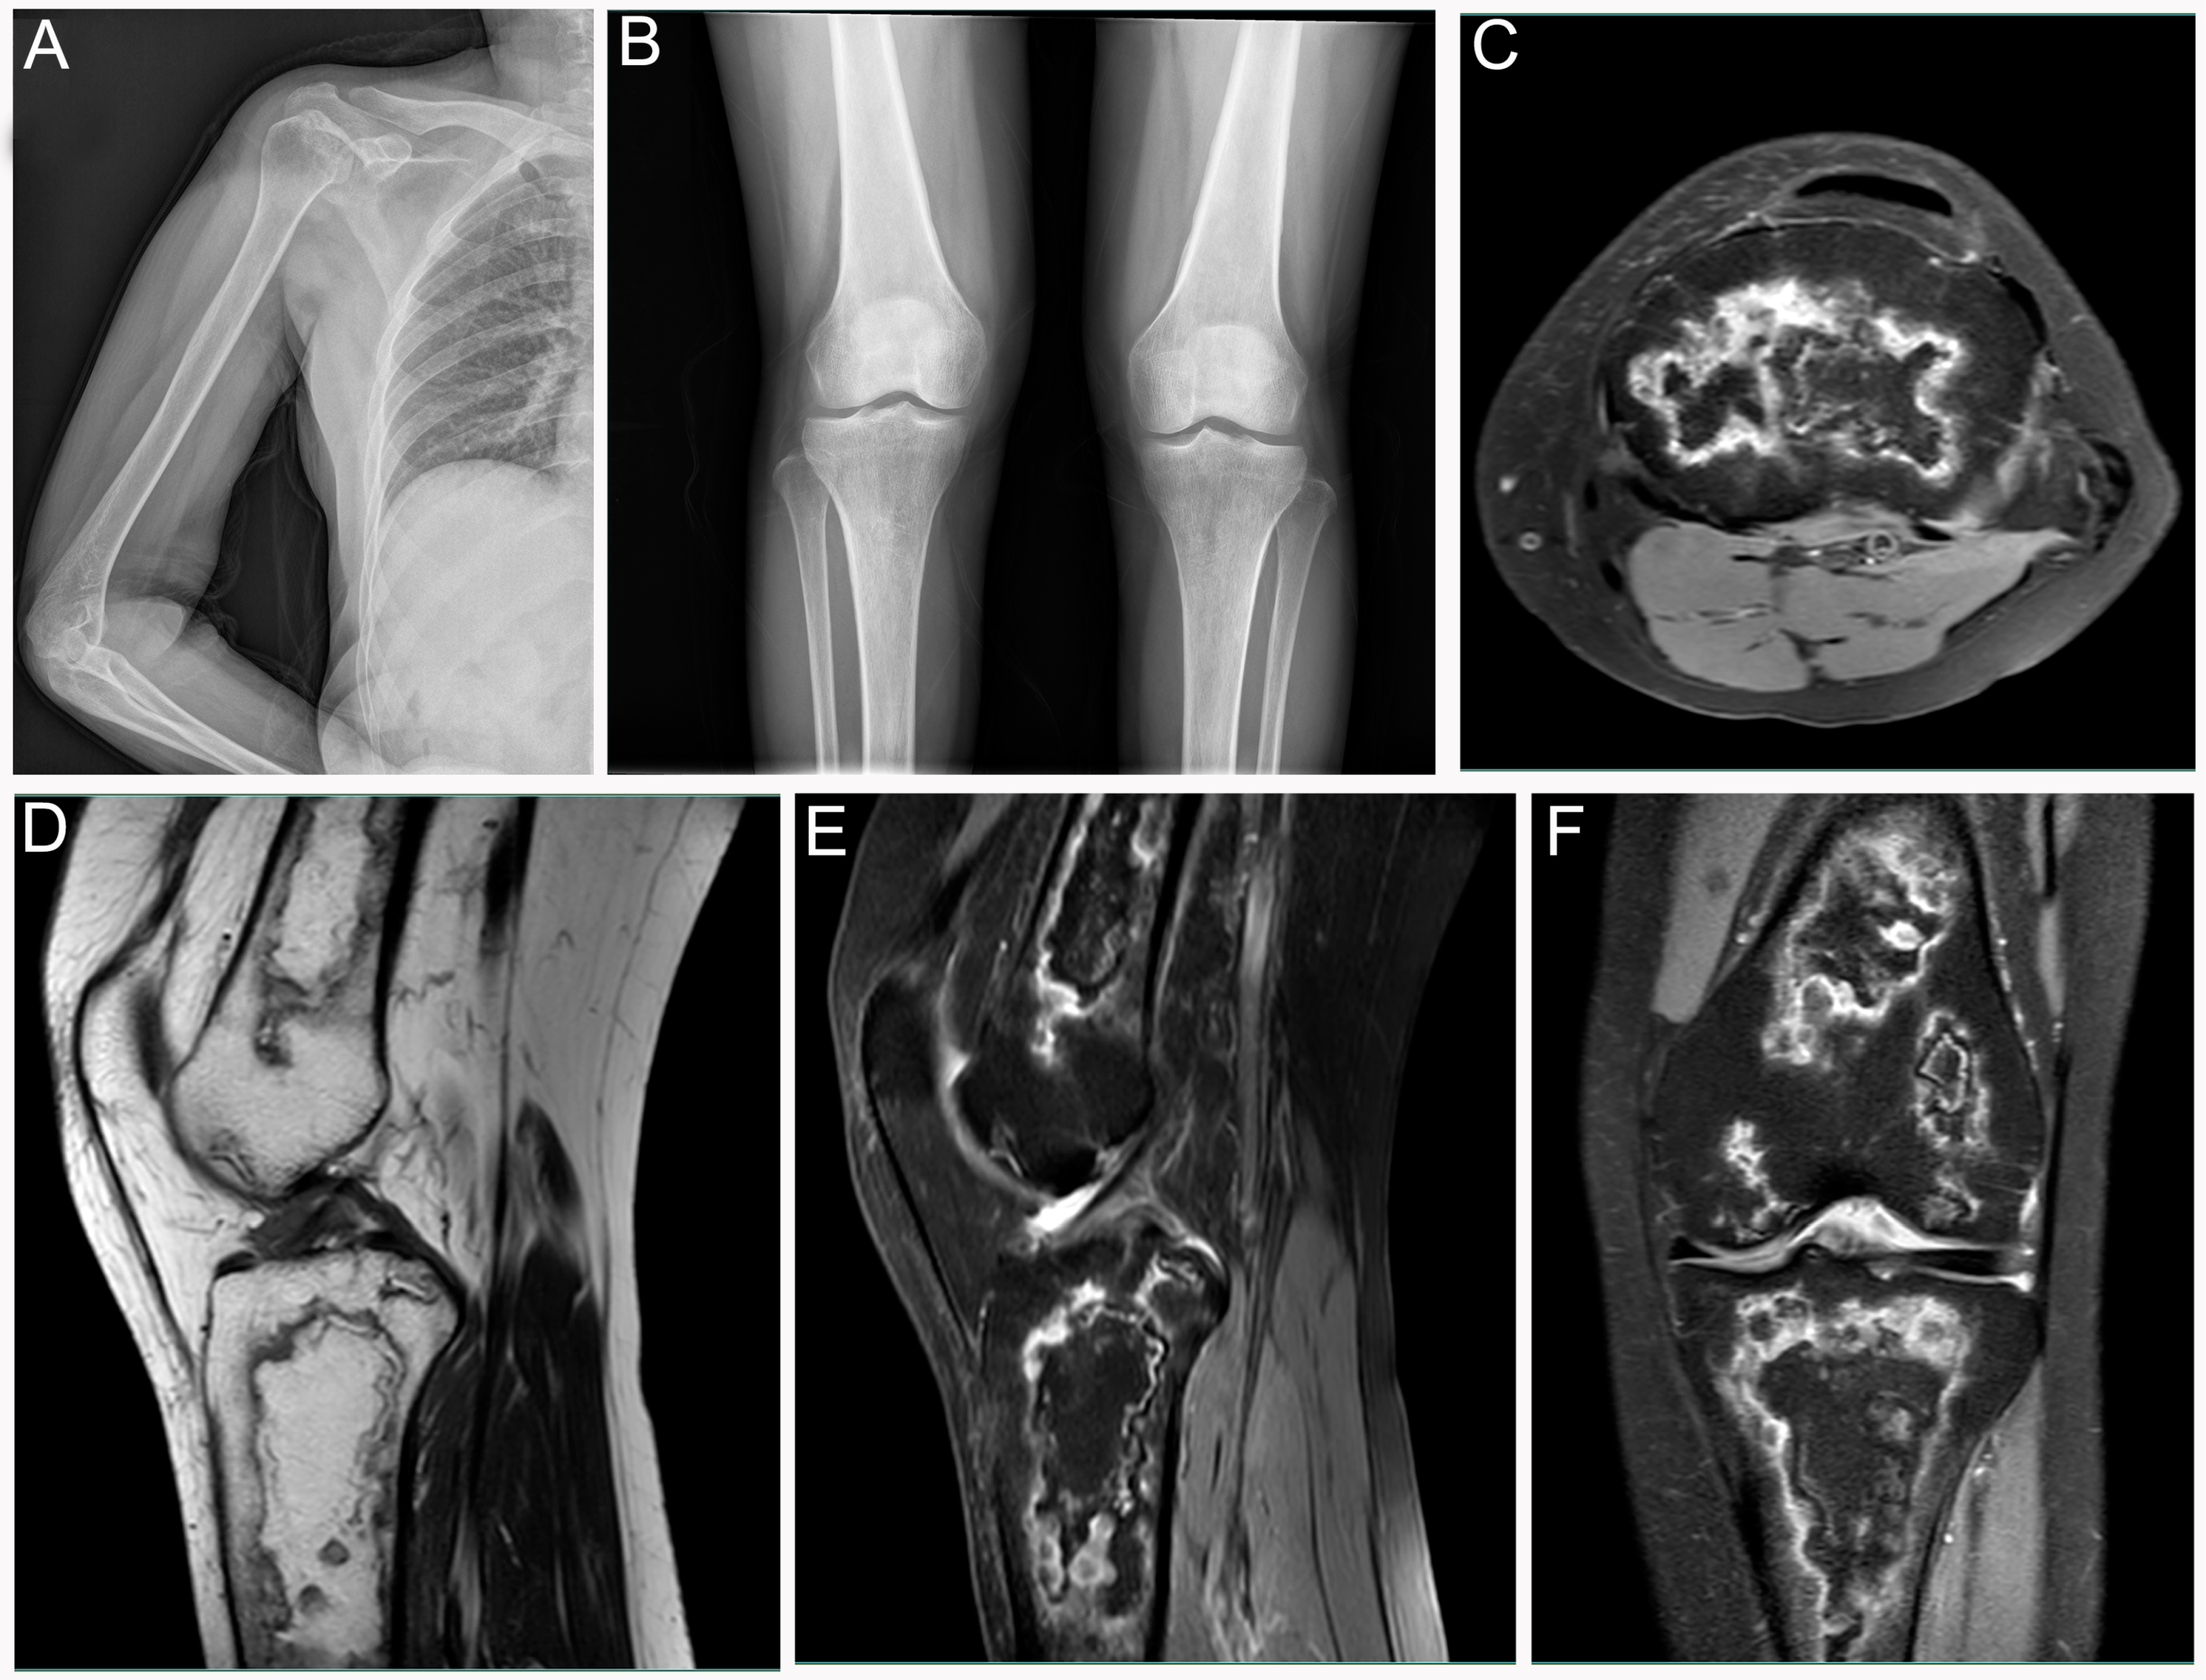

Diagnosis of Bone and Joint Disorders (6-Volume Set): Donald

Diagnosis of Bone and Joint Disorders (6-Volume Set): Donald,

Diagnosis of Bone and Joint Disorders (6-Volume Set): Donald, Diagnosis of Bone and Joint Disorders (6-Volume Set): Donald,

Diagnosis of Bone and Joint Disorders (6-Volume Set): Donald, Diagnosis of Bone and Joint Disorders (6-Volume Set): Donald,

Diagnosis of Bone and Joint Disorders (6-Volume Set): Donald, Diagnosis of Bone and Joint Disorders: Resnick, Donald,

Diagnosis of Bone and Joint Disorders: Resnick, Donald, Differential Diagnosis of Rare Diseases Involving Bilateral,

Differential Diagnosis of Rare Diseases Involving Bilateral, Differential Diagnosis of Rare Diseases Involving Bilateral,